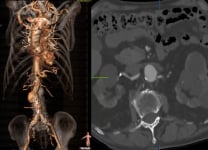

Treatment of recurrent endoleak type II